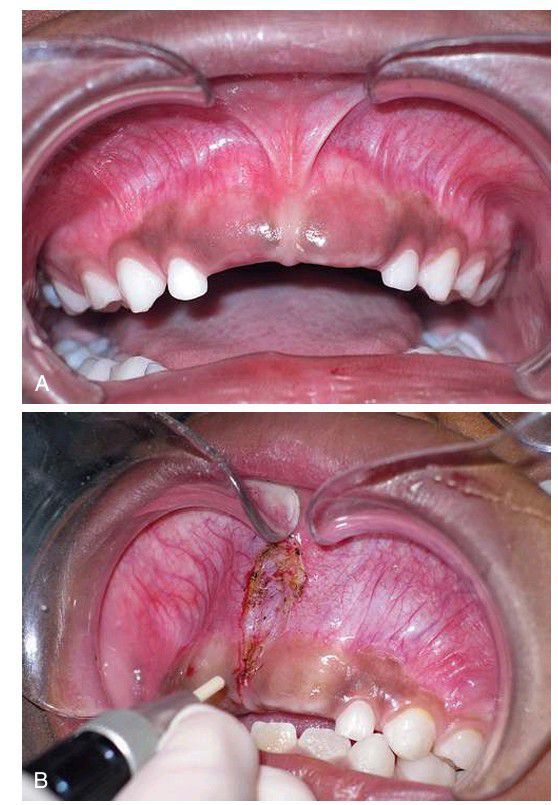

Laser excision of the frenum

. (A) Broad-based frenum in the anterior maxilla. (B) Supraperiosteal ablation of mucosal and dense fibrous frenal attachments. Healing occurs by secondary epithelialization